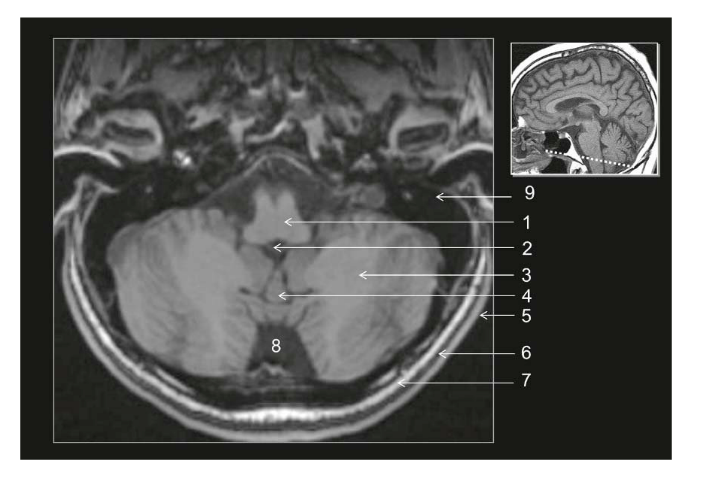

Coupe ?

Légende ?

Coupe ? Légende ?